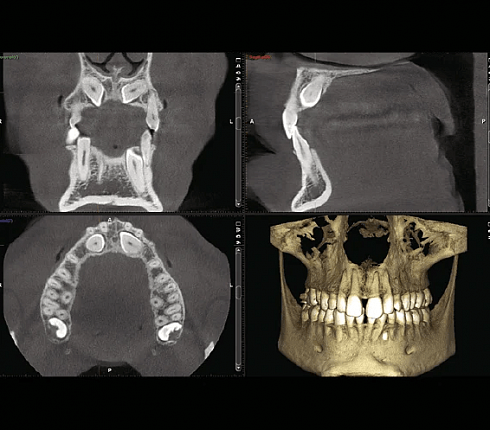

Рентген Planmeca ProMax ® 3D Classic предназначен для получения полной информации об анатомии Вашего пациента в мельчайших подробностях. Этот «умный» и многофункциональный рентгеновский аппарат обеспечит цифровые панорамные, цефалометрические и 3D изображения, а также 3D-фотографии и 3D-сканирование моделей

Planmeca ProMax 3D Classic Ceph – идеальная установка для получения трёхмерных изображений нижней и верхней челюсти, поэтому она отлично подходит для широкого спектра применения в имплантологии, челюстно-лицевой хирургии, пародонтологии, ортодонтии, исследовании височно-нижнечелюстного сустава, исследовании пазух, цефалометрии и пр. Данная гибридная установка объединяет в себе все функции классического ортопантомографа с цефалостатом и современные 3D-технологии для получения объёмных изображений.

- Размеры исследуемых объёмных областей: 140 x 105 x 130 мм (сшитый); 80 х 80 мм (для детей — 68 х 68 мм); 80 х 50 мм (для детей — 68 х 42 мм); 40 х 80 мм (для детей — 34 х 68 мм); 40х50 мм (для детей — 34х42 мм).